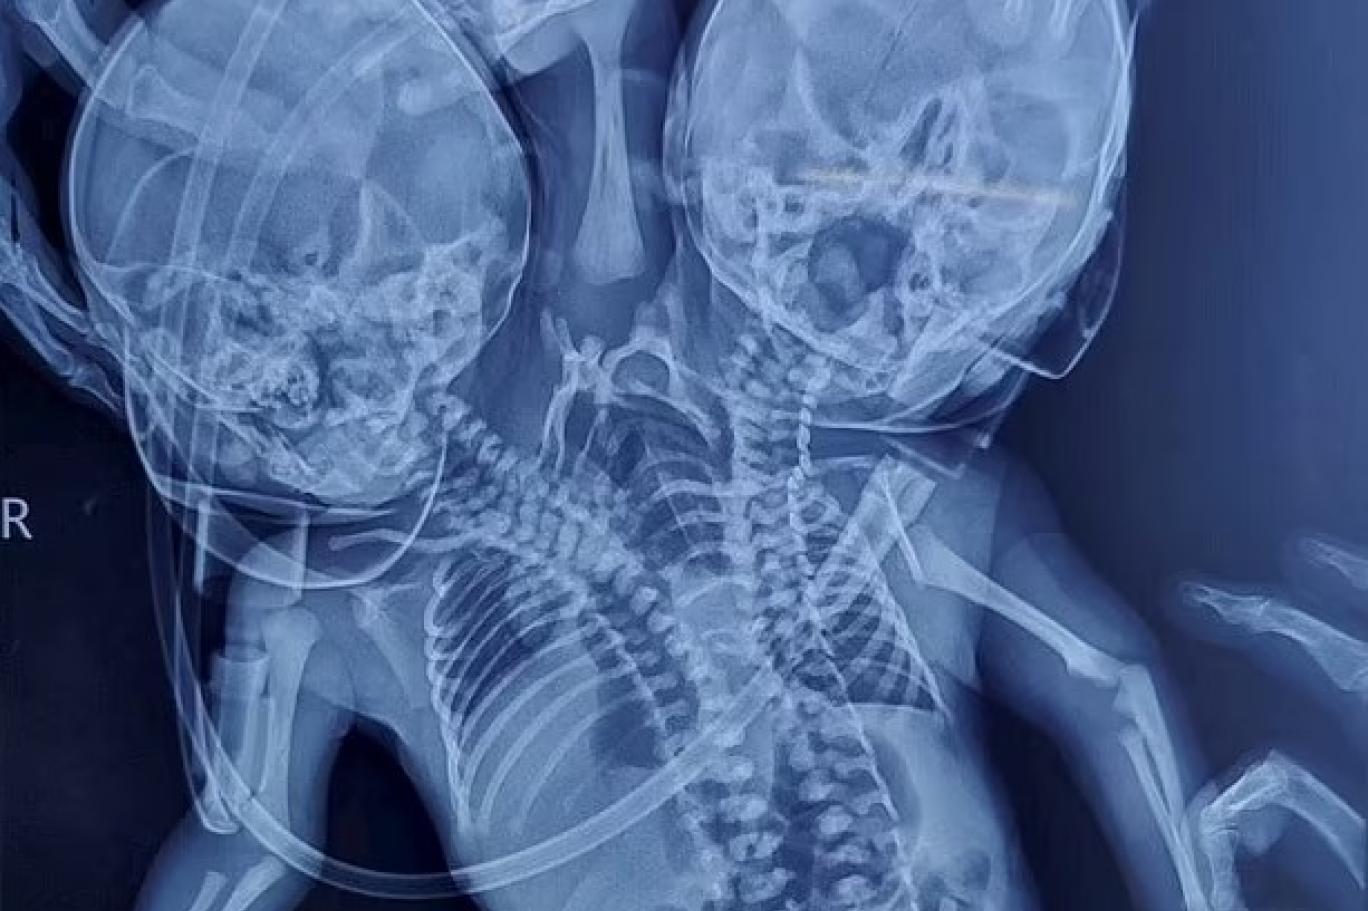

بھارت میں پیدا ہونے والے جڑواں بچوں کا ایک ایکسرے (تصویر: ڈیلی میل/ ایس ڈبلیو این ایس)

بھارت میں ڈاکٹروں کا کہنا ہے کہ ایک ماں کے ہاں ایسا بچہ پیدا ہوا ہے جس کے ایک نایاب بیماری کی وجہ سے دو سر، تین بازو اور دو دل ہیں۔

اس حالت کو ڈائسفیلک پیراپیگس کہا جاتا ہے - جہاں دو شیر خوار بچے ایک دھڑ سے جڑے ہوتے ہیں۔ اکثر اس کے نتیجے میں مردہ بچے کی پیدائش ہوتی ہے۔